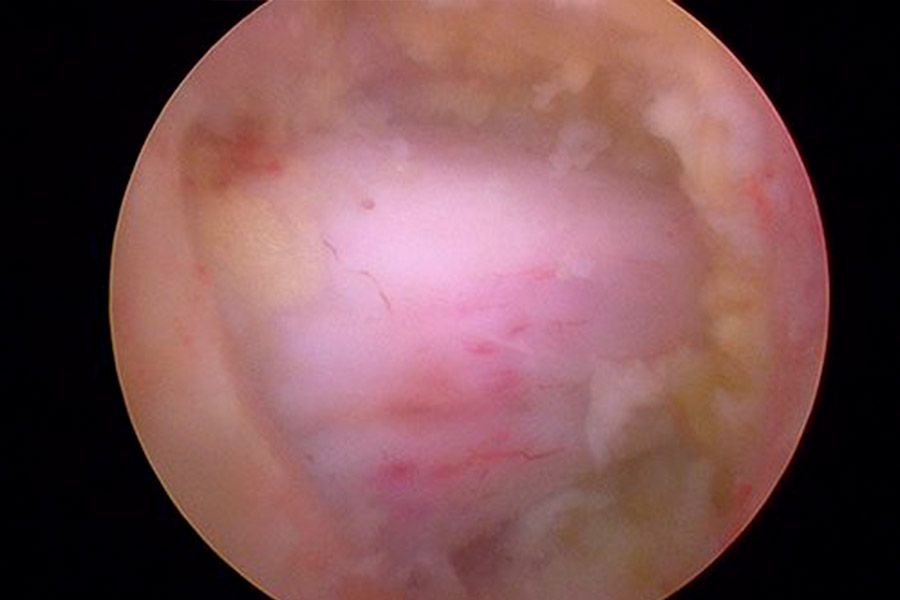

Caso clínico: endoscopia de columna multinivel L4L5 y L5S1

Los síntomas que presentaba el paciente eran dolores acentuados en las piernas, claudicación a la marcha y calambres y hormigueos en las piernas.

Durante la intervención quirúrgica, se abordarán los dos niveles mediante la técnica de endoscopia de columna.